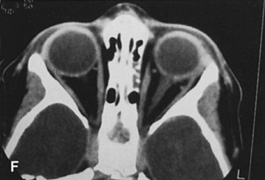

Fig. 25. A,B. Coronal (A) and axial (B) CT scans demonstrating well-encapsulated mass posteriorly in the superonasal orbit. An excellent alternative to transcranial orbitotomy for this lesion is an anterior approach via a vertical-lid splitting incision.

VERTICAL-LID-SPLIT SUPERIOR ORBITOTOMY

The upper eyelid crease incision gives excellent access to the peripheral superior orbital space. However, lesions that lie intraconally are difficult to approach with a transverse lid crease incision as dissection must be performed medial to the medial horn of the levator muscle to avoid transecting and disinserting the levator aponeurosis and Müller's muscle. However, vertically splitting the upper lid allows a vertical separation of the levator aponeurosis and Müller's muscle and does not disinsert it from its normal insertions on the tarsal plate. This approach provides an excellent exposure of the superomedial orbit and is useful for approaching lesions that lie medial to the optic nerve.26 In this situation, it is often an attractive alternative to a transcranial superior orbitotomy, which might otherwise be required (Fig. 25).